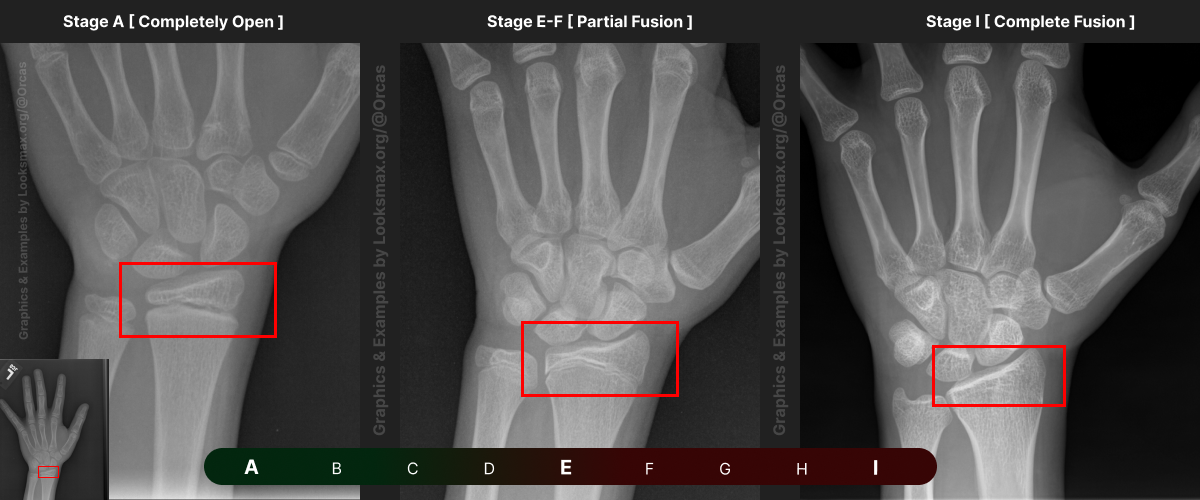

I added references for stages A (Completely unfused), E-F (Partial fusion, basically late stages of puberty), and I (Complete Fusion)

You will have to eyeball this now using your own xrays, I’ve given three examples and some wiggle-room for letters using a reference bar (green-red) below the image, write down your estimated guesses in a text file until you finish all 13 bones.

Don’t doubt yourself, eyeballing isn’t perfect but it still works well, just choose & continue.

Ex.

“My Radius looks more fused than the image from E-F, but its not as fused as I, it’s closer to the 2nd picture though, so I’ll rate it G” And continue

Bonetype: Radius (distal end)

Check & use the chart below to figure out where you are. Then write your result on a piece of paper or a text file.